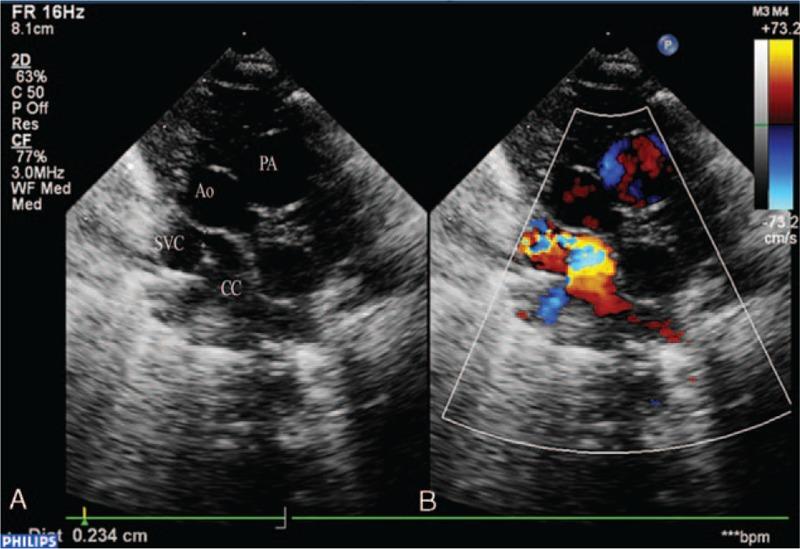

Total anomalous pulmonary venous connection is an uncommon congenital heart disease. Four types are described based on the site of pulmonary venous drainage: supracardiac, cardiac, infradiaphragmathic, and mixed connection. In most cases of supracardiac type, the common venous confluence drains through an ascending left vertical vein into the brachiocephalic vein, right superior vena cava, and then into the right atrium. Anomalous connection of the pulmonary venous confluence directly to the right SVC, especially the obstructed form is an unusual and severe supracardiac variant. The prenatal diagnosis is challenging.

The 4-chamber view showed a small left atrium, with a "smooth" posterior wall and the absence of pulmonary vein connection. This is the first case of prenatally diagnosed isolated, obstructed supracardiac type with drainage directly into the right superior vena cava.

四腔心切面显示左心房小,后壁“光滑”且无肺静脉连接。这是首例产前诊断为孤立性、梗阻性心上型且直接引流至右上腔静脉的病例。